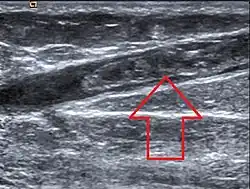

| Ultrasonographic image showing thrombosis of the great saphenous vein. | |